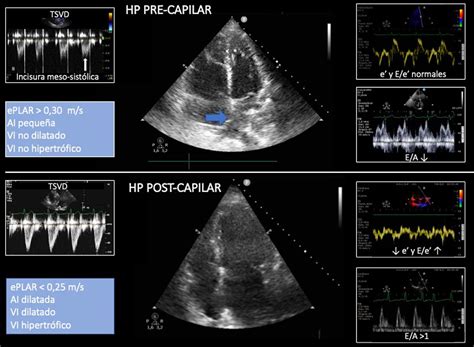

El diagnóstico de la HPP requiere la demostración de hipertensión pulmonar mediante cateterismo cardíaco derecho, con medición de la presión arterial pulmonar media (PAPm) ≥ 20 mmHg, presión de oclusión de la arteria pulmonar (PCAP) ≤ 15 mmHg y resistencia vascular pulmonar (RVP) > 3 unidades Wood. Es crucial excluir otras causas de HAP. La ecocardiografía es una herramienta no invasiva importante para la evaluación inicial, estimando la presión sistólica de la arteria pulmonar y evaluando la función del ventrículo derecho.